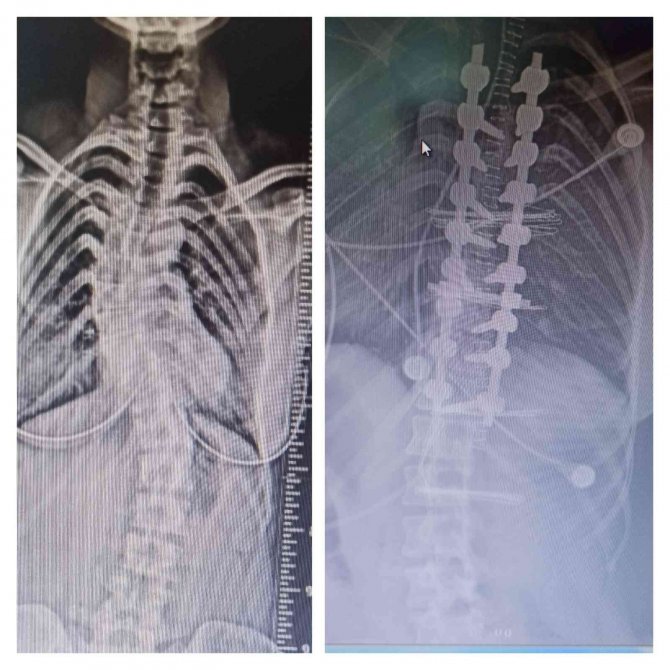

Balıkesir Atatürk Şehir Hastanesi bünyesinde ilk kez yapılan omurga eğriliği ameliyatı ile 21 yaşındaki hasta sağlığına kavuşturuldu.

Omurga eğriliği teşhisi ile Balıkesir Atatürk Şehir Hastanesine başvuran 21 yaşındaki hasta, ortopedi uzmanları Op. Dr. Ali Ertuğrul ve Op. Dr. İrfan Tepe tarafından ameliyat edilip taburcu edildi. Toplum genelinde skolyoz görünme sıklığı yüzde 2-4 arasında. Kız çocuklarında erkeklere göre görünme sıklığı çok daha fazla.

Ameliyatı ortopedi uzmanları Op. Dr. Ali Ertuğrul ve Op. Dr. İrfan Tepe gerçekleştirdi. Ameliyatı yapan doktorlardan Ali Ertuğrul, "Genç hastamızın skolyana bağlı ağır omurga eğriliği vardı. Hastalığın gelişimine göre ameliyat edilmesi elzem bir hal aldı. Bizler ameliyatı planladık ve özel yapım malzemeler kullanarak omurga vidası ile düzeltme sağladık. İdeopatikSkolyoz (omurga eğriliği)hastanemizde ilk defa yapıyoruz. Balıkesir'imize vereceğimiz sağlık hizmet çeşidini arttırmanın mutluluğunu ve gururunu yaşıyoruz" dedi.

Ertuğrul, çocuklarda omurga eğriliği ve kamburluk cerrahisinin artık Balıkesir Atatürk Şehir Hastanesinde yapılabilir hale geldiğini de sözlerine ekledi.